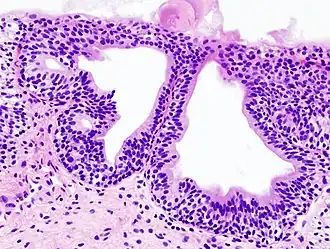

Histopatología de una cistitis glandular en una biopsia citoscópica. Tinción con hematoxilina y eosina. | ||

Puede tener distintas causas. La causa más frecuente de cistitis es la infección por bacterias gramnegativas, destacando entre todas la Escherichia coli. Para que un germen produzca cistitis primero debe colonizar la orina de la vejiga (bacteriuria) y posteriormente producir una respuesta inflamatoria en la mucosa vesical. A esta forma de cistitis se le denomina cistitis bacteriana aguda. Afecta a personas de todas las edades, aunque sobre todo a mujeres en edad fértil o a ancianos de ambos sexos. Otras formas de cistitis son la cistitis tuberculosa (producida en el contexto de una infección tuberculosa del aparato urinario), la cistitis química (causada por efectos tóxicos directos de algunas sustancias sobre la mucosa vesical, por ejemplo la ciclofosfamida), la cistitis rádica (secuela crónica de tratamientos con radioterapia sobre la pelvis), la cistitis glandular (una metaplasia epitelial con potencialidad premaligna) o la cistitis intersticial (una enfermedad funcional crónica que cursa con dolor pélvico, urgencia y frecuencia miccional).